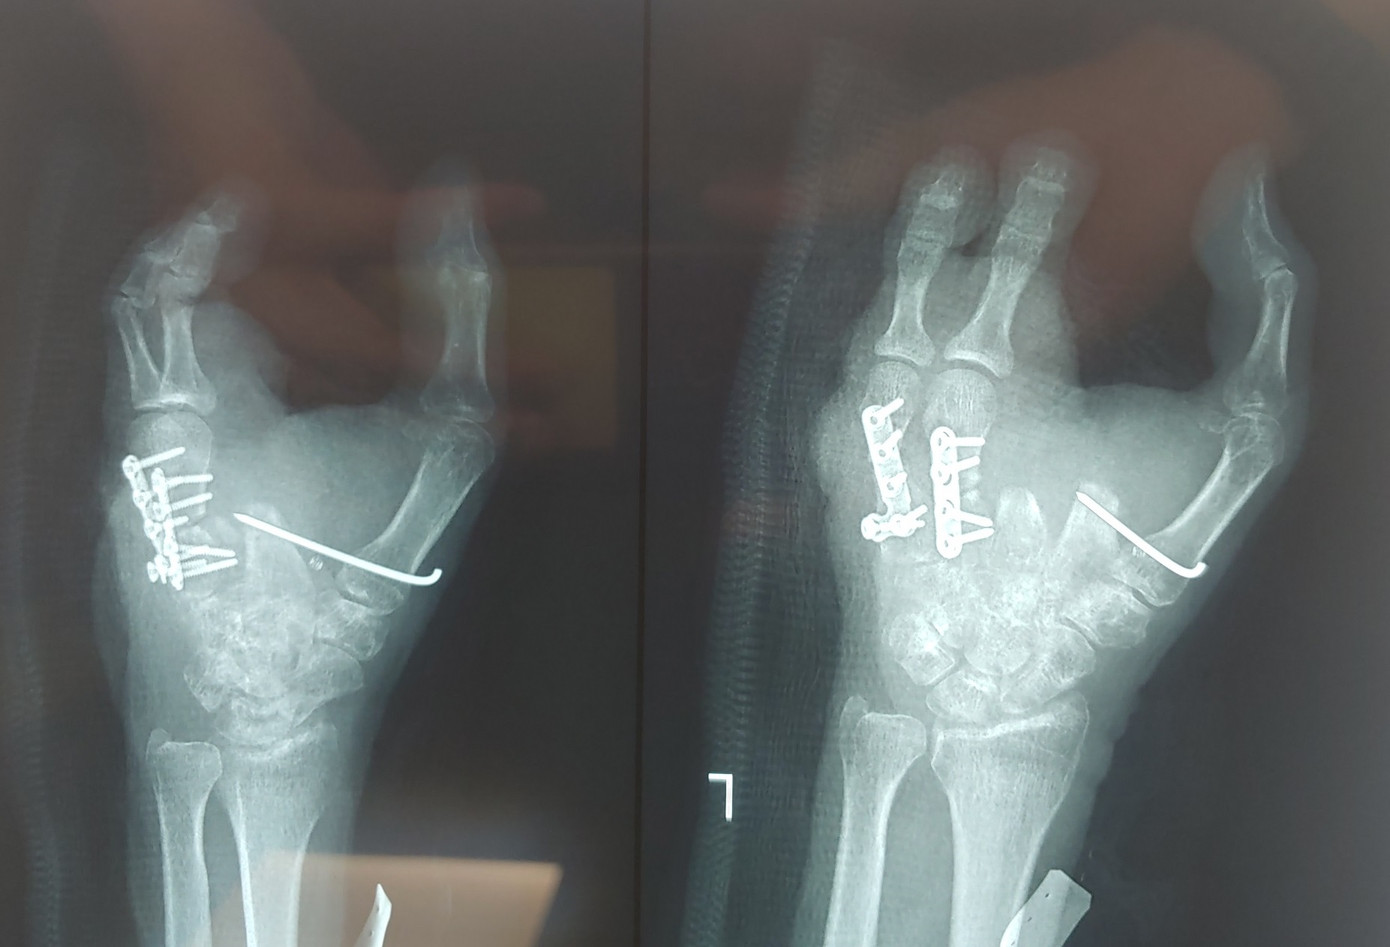

Sau 6 giờ khẩn trương trong phòng mổ, các bác sĩ đã phẫu thuật lấy ngón chân thứ 2 và 3 của bàn chân trái ghép lên vị trí của ngón 4 và 5 của bàn tay trái nhằm tạo cung cầm nắm giúp bệnh nhân. Kíp mổ thực hiện kết xương từ ngón chân lên bàn tay, khâu nối mạch máu, dây thần kinh, gân cơ từ 2 ngón chân với mạch máu 2 ngón tay.

| Các bác sĩ đã thực hiện thành công cuộc phẫu thuật chuyển 2 ngón chân lên làm 2 ngón tay |

“Các công đoạn ghép ngón tay này gồm nhiều kỹ thuật, việc khâu nối mạch máu và thần kinh ở những trường hợp này rất phức tạp. Trong quá trình phẫu thuật bóc tách vạt ngón chân phải bảo tồn được nguồn mạch nuôi của ngón, đòi hỏi phẫu thuật viên có nhiều kinh nghiệm. Khâu mạch máu và thần kinh bằng kĩ thuật khâu nối vi phẫu, do mạch máu và thần kinh nhỏ nên khâu nối khó khăn, nên cần các phương tiện máy móc hiện đại của bệnh viện” BS Thành Nhơn nói.